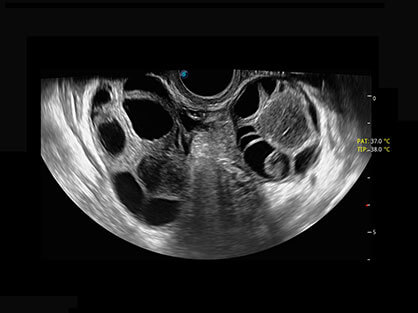

卵泡结构的自动识别和测量,可显示多组测量数据。

大角度腔内容积探头,可完整包络子宫及盆底结构,充分展示组织结构毗邻关系。